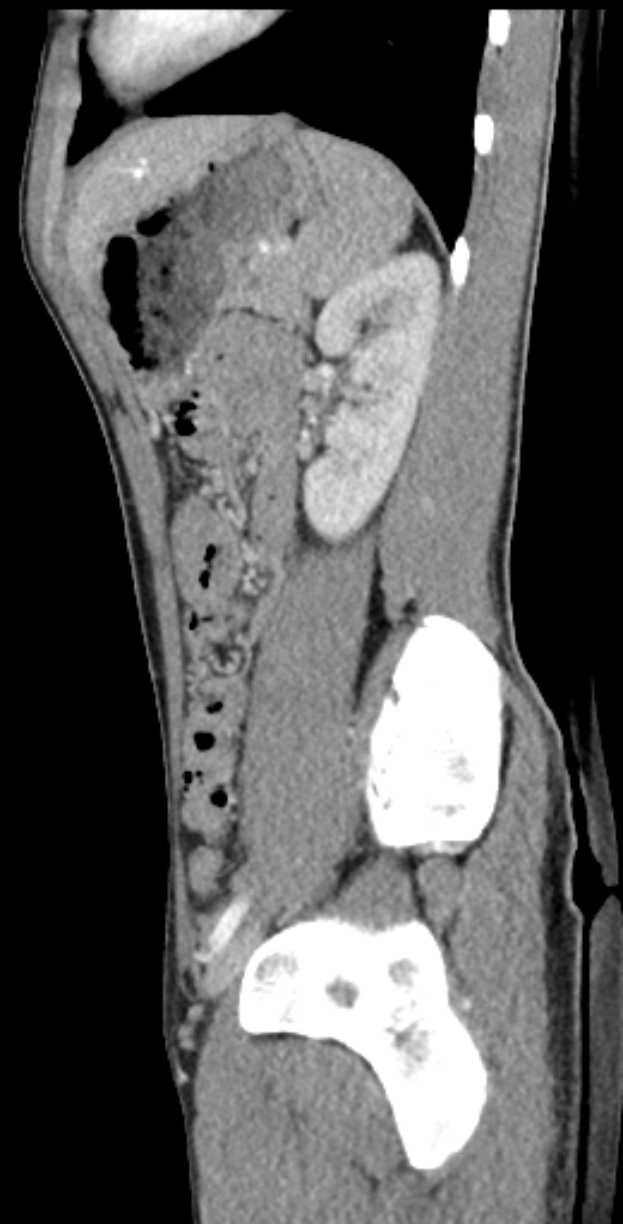

Eine MRT-Aufnahme eines Knies, die einen Riss in der Mitte zeigt, umgeben von einem dunklen Hintergrund.Franco Gröttner

Muskelverletzungen: Köln vorerst ohne Thielmann und Sebulonsen - 1. FC Köln verliert zwei Leistungsträger durch Muskelverletzungen im Hoffenheim-Spiel

1. FC Köln steht vor neuen Verletzungssorgen, nachdem zwei Leistungsträger im selben Spiel ausgefallen sind. Jan Thielmann und Sebastian Sebulonsen litten während der Partie gegen die TSG Hoffenheim unter Muskelproblemen. Ihre Ausfälle verschärfen die wachsenden Fitnessprobleme des FC. Die Schwierigkeiten begannen bereits vor dem Anpfiff: Thielmann musste sein Aufwärmtraining abbrechen und konnte nicht von Beginn an spielen. Kurzfristig sprang Eric Martel für ihn ein. Während des Spiels hatte auch Sebulonsen mit Beschwerden zu kämpfen. Er hielt bis zur 69. Minute durch, ehe er wegen einer Muskelverletzung ausgewechselt werden musste. Die Verletzungen fehlen dem FC nun vorerst zwei wichtige Kadermitglieder. Beide Spieler hatten in der aktuellen Bundesliga-Saison bisher kaum Spielpraxis sammeln können, bevor sie zurückgeworfen wurden. Das genaue Ausmaß ihrer Verletzungen ist noch unklar, doch beide werden nun weiteren Untersuchungen unterzogen. Der Doppelschlag trifft den 1. FC Köln zu einem ungünstigen Zeitpunkt. Mit Thielmann und Sebulonsen an der Seitenlinie muss die Mannschaft ihre Planung für die kommenden Spiele anpassen. Wie lange der Verein auf die beiden verzichten muss, hängt von ihren Genesungszeiten ab.